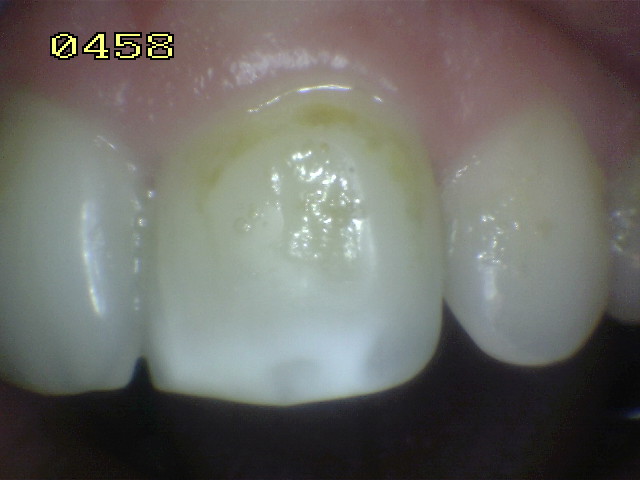

Una morfología de la fisura estrecha, con forma de botella de "Coca-Cola" genera un nicho ecológico ideal para la colonización de cualquier bacteria productora de ácidos. Al no poder remover en forma períodica dicho biofilm de una zona tan estrecha, el ataque ácido genera una lesión cariosa en la dentina, con un aspecto de esmalte intacto a la inspección visual, o sea un típico código 3 y 4 de ICDAS Completo. (Caries Moderada para el ICDAS COMBINADO)

Imagen digital que representa la microfiltración y penetración del sellante realizado.

Microfotografía: Muestra como el sellador obtura la caries subyascente, evitando su avance.

Código 3 (Caries moderada) in vitro. Los códigos 3 in vivo debe ser sellado para evitar el avance del proceso carioso. (MNO)

Código 4 (Caries moderada) in vitro. Los códigos 4 in vivo deben ser tratados en forma operatoria con preservación dental (MOPD), porque presentan dentina infectada.